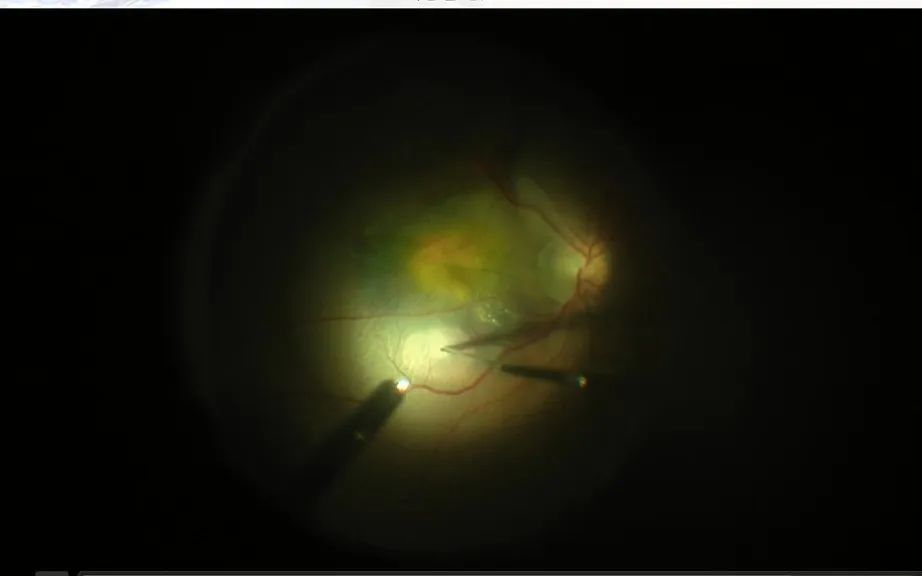

其次,我来说说这个手术,我们采用25G微创手术器械在眼睛巩膜(白眼球)上打三个 直径仅0.5mm 的小孔,建立手术通路,通过 每分钟10000次 的高切速微创玻璃体切割机切除玻璃体,再利用 41G(类似头发丝粗细)细微眼内注射针 向视网膜下出血区注射约0.1ml(含25ug)药物——这是该手术治疗的 超级微创性 。因此,该技术需要医生有娴熟的微创玻璃体切除技术和沉稳的心理素质,能丝毫不差的在微米级的空间范围将药物准确地直接注射到黄斑视网膜下出血区,促进出血吸收且移行离开黄斑区,以达到精准治疗、恢复视力的目的。

(微细针将药物准确注入出血区)

再次,按赵本山赵爷的话说,不看广告看疗效,在这个手术中,药物注射后我们医生立即能看到视网膜下积血明显变淡,当然为了保证更好的效果,我们还要在缝合手术切口后在玻璃体腔内填充一种长效气体,以顶压视网膜、驱使溶解的视网膜下积血离开黄斑区——这是该手术的 疗效迅速性 。